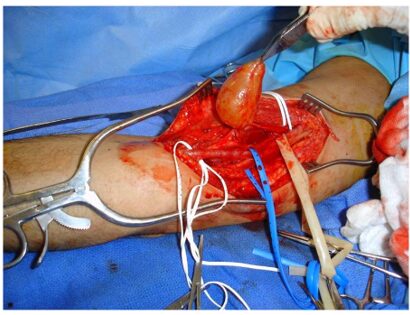

Intra-Op: Specimen Photo

This is an intraoperative photo of a schwannoma, a common benign soft-tissue tumor.